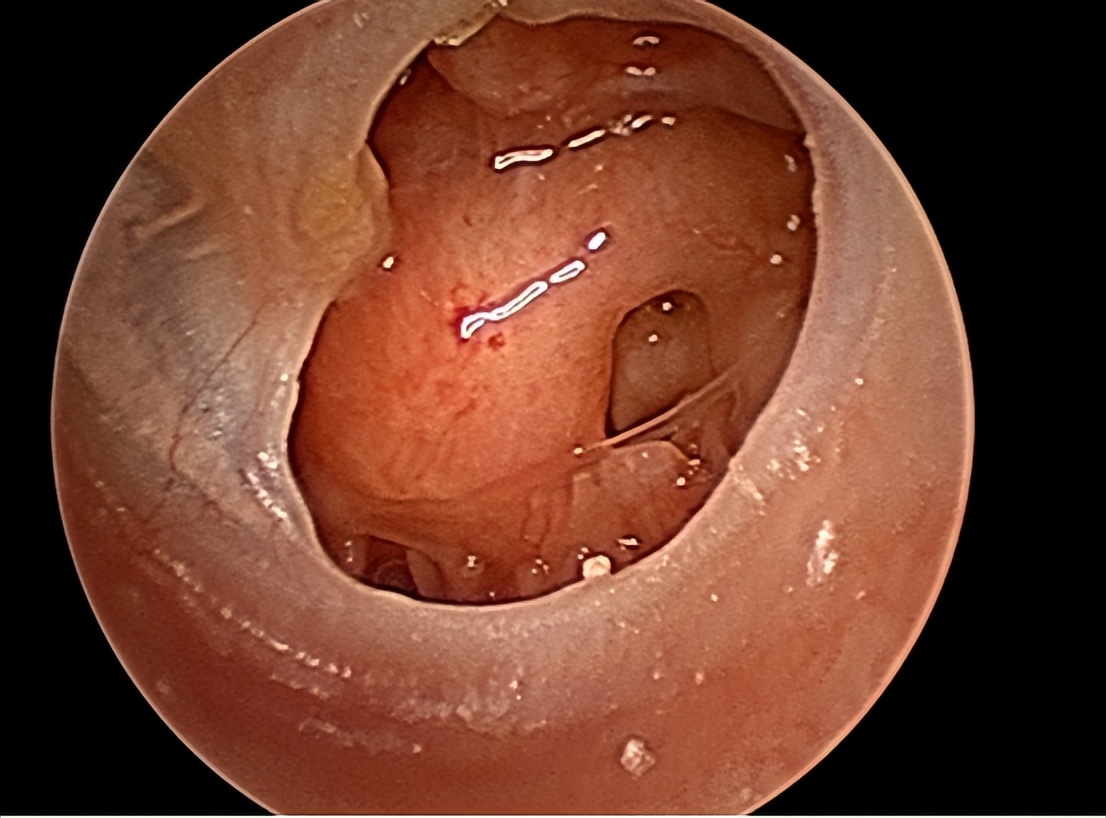

1.鼓膜置管术

指南建议在手术干预前应有3个月的观察等待。鼓膜置管术是治疗SOM的主要方法,尤其是不满4岁的儿童。其主要是在耳内镜或显微镜下进行操作,可快速有效促进鼓室渗出液排出,使鼓室与外界气压达到平衡。

然而无法短时间内缓解局部炎症,操作不慎可导致外耳道血肿、听骨链受损、鼓室粘连、永久性鼓膜穿孔等风险,不利于患儿预后,所以需要严格把握手术指征。